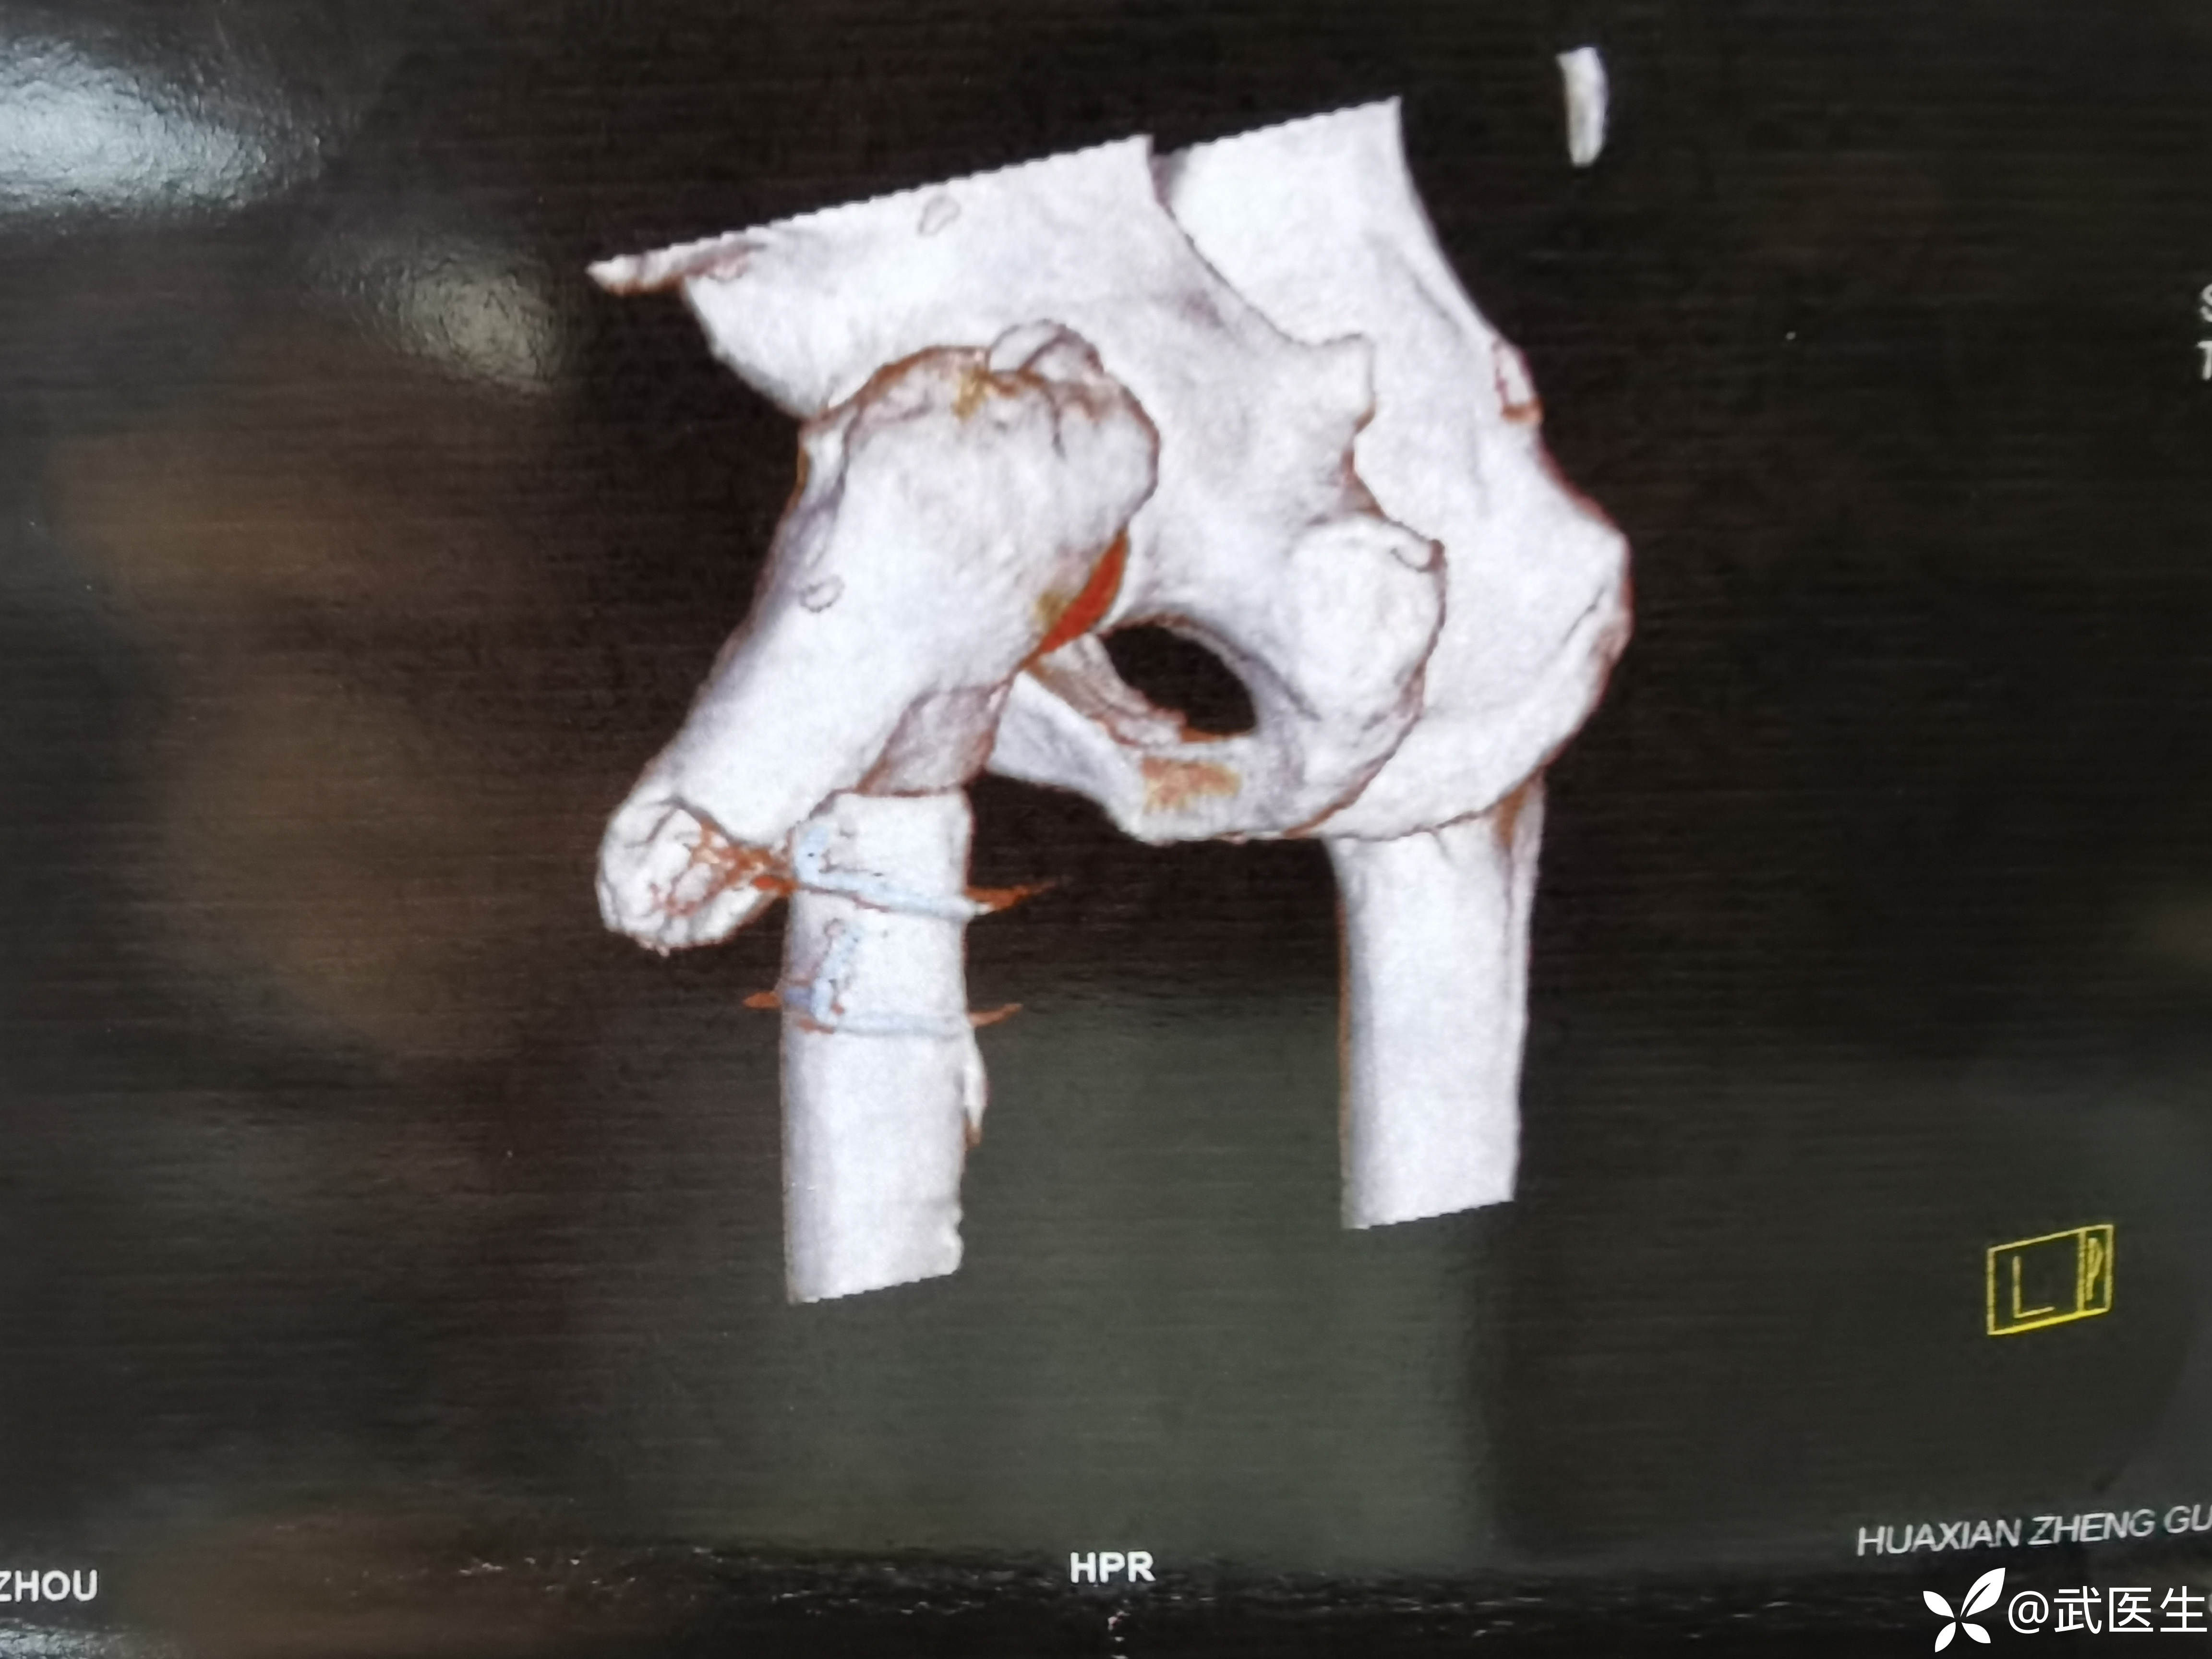

CT如下,典型股骨近端骨折移位方向